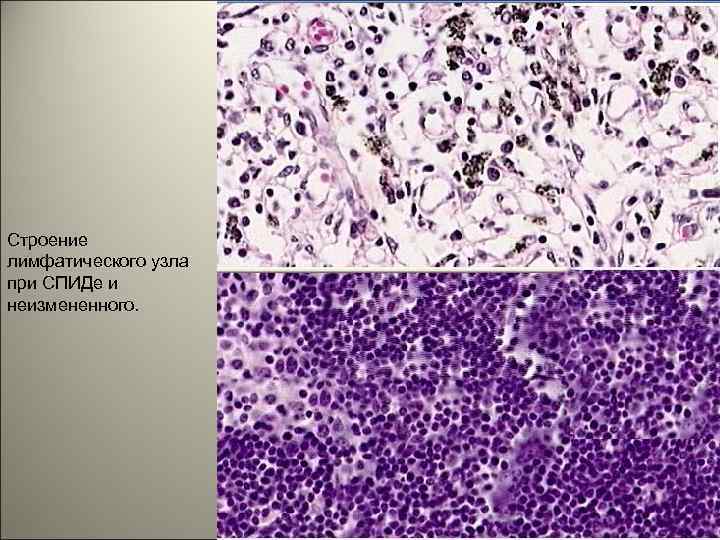

Строение лимфатического узла при СПИДе и неизмененного. 6